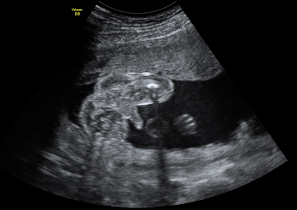

Las ecografías en 4D realizadas en la semana 20 de embarazo permiten ver el sexo femenino del feto con nitidez. En este caso, se ha capturado la imagen de los genitales femeninos, en concreto, la vulva.

Ecografía: Genitales de una niña de 20 semanas

En este ultrasonido, podemos ver la vulva del feto y otros pequeños detalles del sexo fetal.